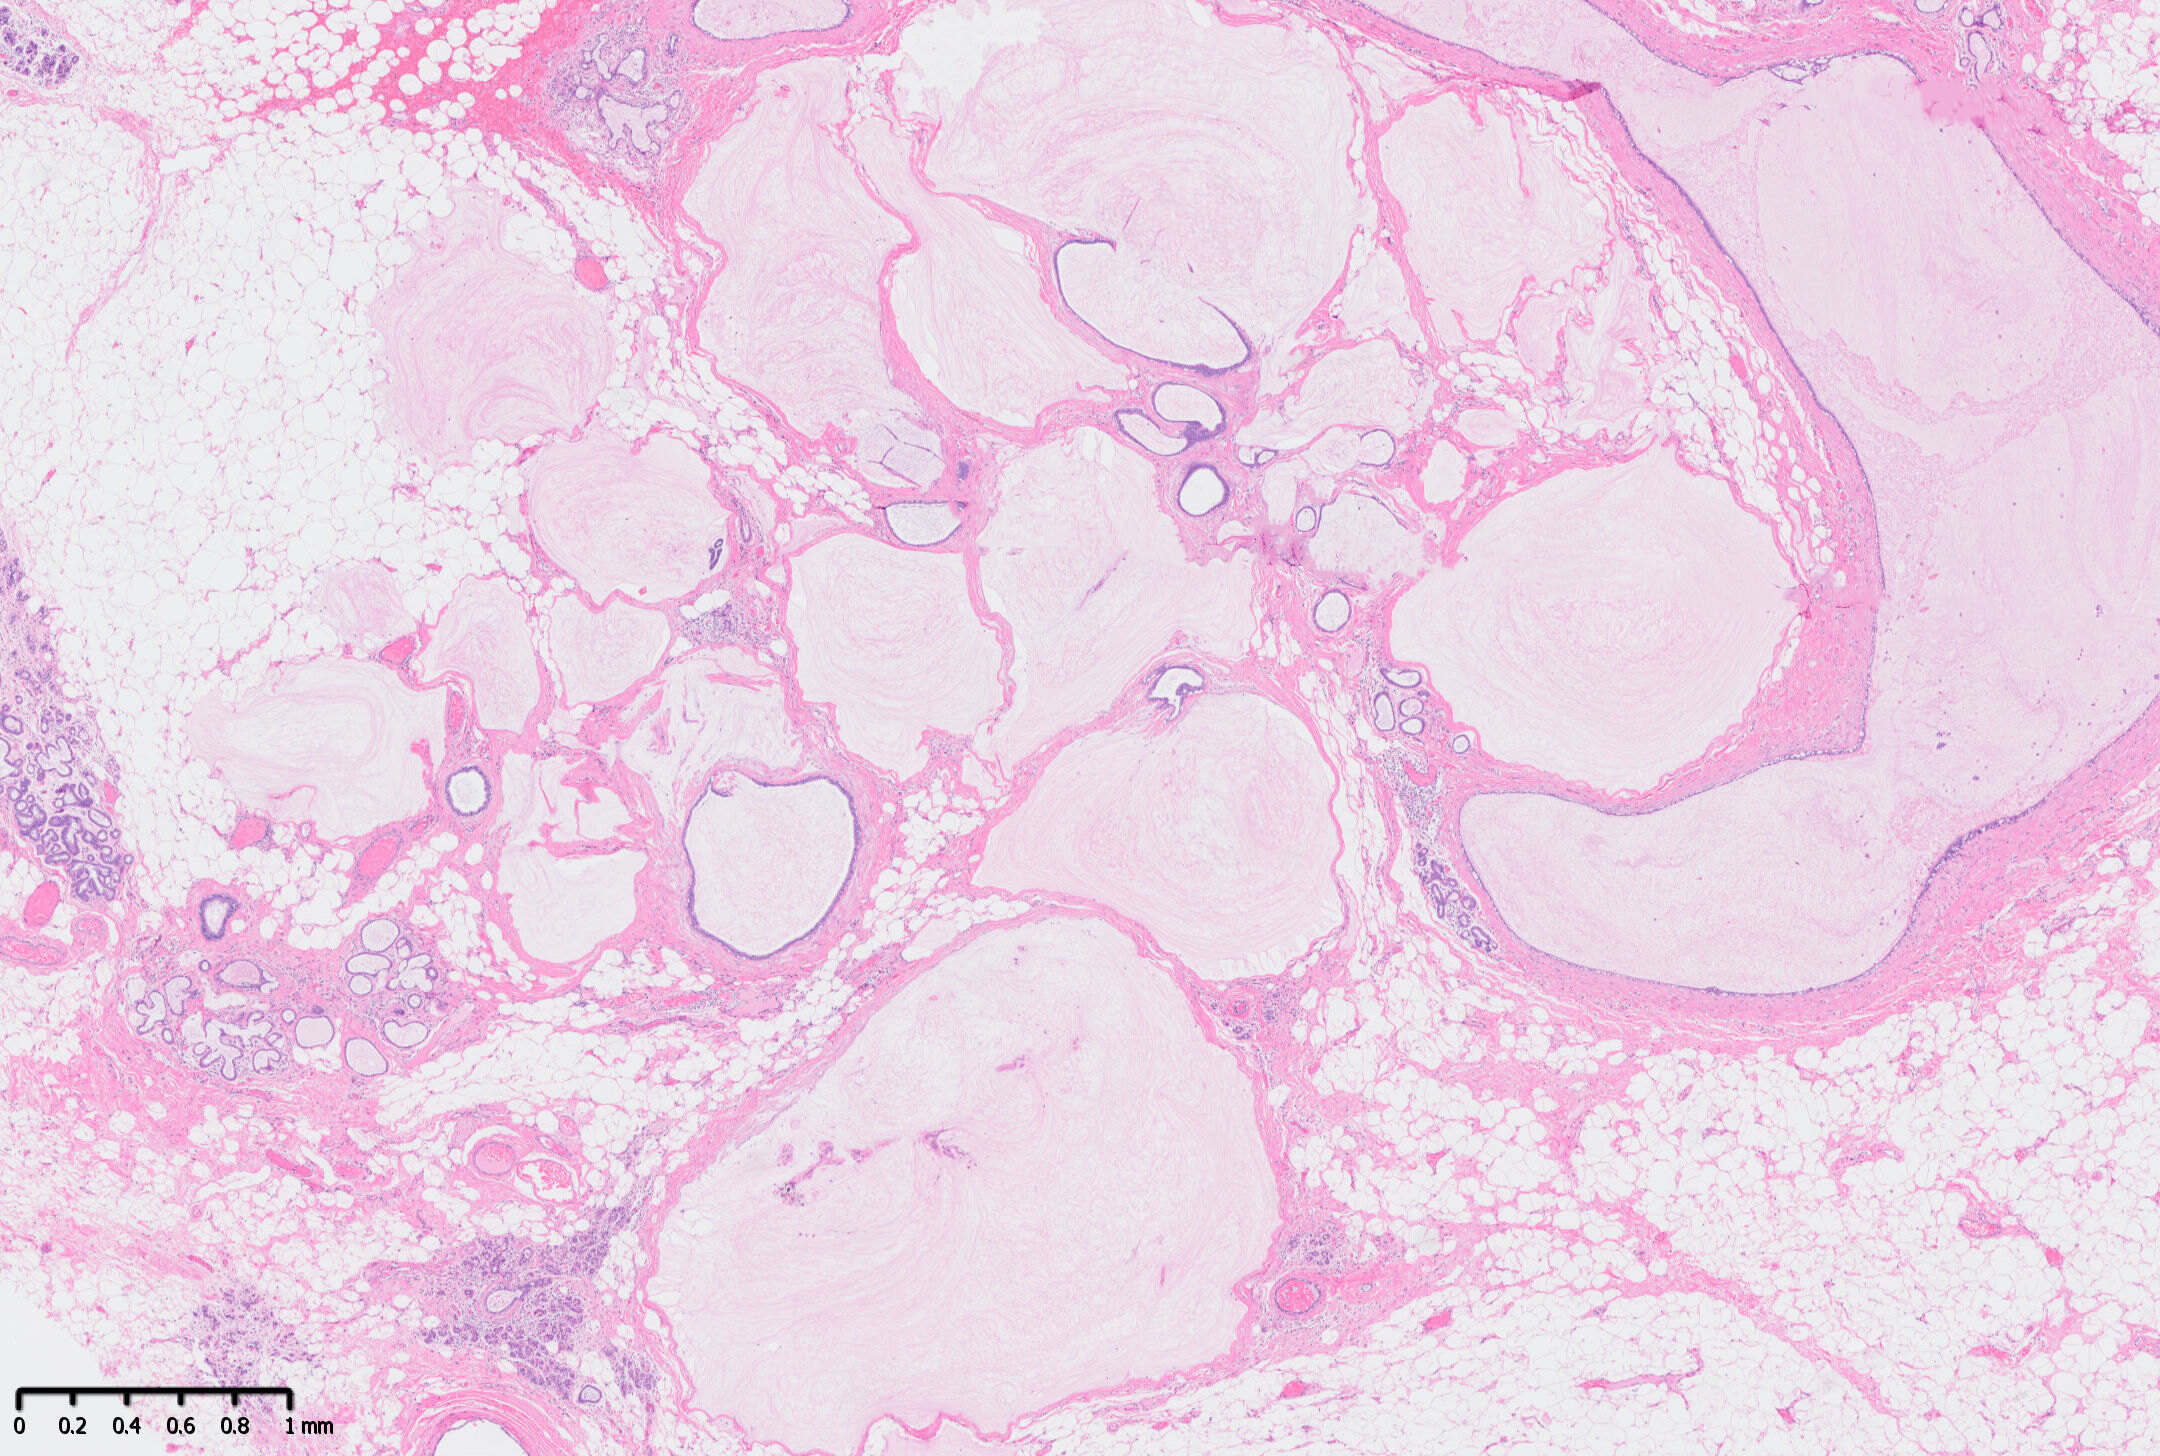

病例分享:乳腺粘液囊肿样病变

乳腺粘液囊肿样病变病理图片

乳腺粘液囊肿样病变(Mucocele-like lesion,MLL),是一种良性囊肿样病变,目前认为其存在一系列组织学谱系:粘液囊肿样病变?伴不典型增生?伴原位癌?浸润性癌。

所以粘液囊肿样病变,一般应以完整肿块切除的手术标本诊断为准,同时病理诊断粘液囊肿样病变时,一方面应充分取材,另一方面临床医生也要引起足够重视,制定相应的随访治疗方案。